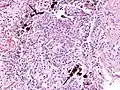

Asbestosis is the scarring of lung tissue (beginning around terminal bronchioles and alveolar ducts and extending into the alveolar walls) resulting from the inhalation of asbestos fibers. There are two types of fibers: amphibole (thin and straight) and serpentine (curly). All forms of asbestos fibers are responsible for human disease as they are able to penetrate deeply into the lungs. When such fibers reach the alveoli (air sacs) in the lung, where oxygen is transferred into the blood, the foreign bodies (asbestos fibers) cause the activation of the lungs' local immune system and provoke an inflammatory reaction dominated by lung macrophages that respond to chemotactic factors activated by the fibers.[19] This inflammatory reaction can be described as chronic rather than acute, with a slow ongoing progression of the immune system attempting to eliminate the foreign fibers. Macrophages phagocytose (ingest) the fibers and stimulate fibroblasts to deposit connective tissue.

Due to the asbestos fibers' natural resistance to digestion, some macrophages are killed and others release inflammatory chemical signals, attracting further lung macrophages and fibrolastic cells that synthesize fibrous scar tissue, which eventually becomes diffuse and can progress in heavily exposed individuals. This tissue can be seen microscopically soon after exposure in animal models. Some asbestos fibers become layered by an iron-containing proteinaceous material (ferruginous body) in cases of heavy exposure where about 10% of the fibers become coated. Most inhaled asbestos fibers remain uncoated. About 20% of the inhaled fibers are transported by cytoskeletal components of the alveolar epithelium to the interstitial compartment of the lung where they interact with macrophages and mesenchymal cells. The cytokines, transforming growth factor beta and tumor necrosis factor alpha, appear to play major roles in the development of scarring inasmuch as the process can be blocked in animal models by preventing the expression of the growth factors.[20][21] The result is fibrosis in the interstitial space, thus asbestosis.

Asbestosis resembles many other diffuse interstitial lung diseases, including other pneumoconiosis. The differential diagnosis includes idiopathic pulmonary fibrosis (IPF), hypersensitivity pneumonitis, sarcoidosis, and others. The presence of pleural plaques may provide supportive evidence of causation by asbestos. Although lung biopsy is usually not necessary, the presence of asbestos bodies in association with pulmonary fibrosis establishes the diagnosis.[25] Conversely, interstitial pulmonary fibrosis in the absence of asbestos bodies is most likely not asbestosis.[11] Asbestos bodies in the absence of fibrosis indicate exposure, not disease.